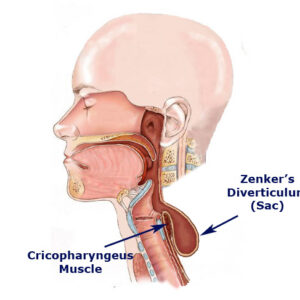

علل

GERD معمولاً باعث رفلاکس اسید می شود که ممکن است در نتیجه عملکرد نامناسب اسفنکتر تحتانی مری (LES) باشد.

LES یک نوار عضلانی مدور در انتهای مری شما است. هنگامی که قورت می دهید، آرام می شود و باز می شود تا غذا و مایعات از دهان به معده بروند. سپس سفت می شود و دوباره بسته می شود.

رفلاکس اسید زمانی اتفاق می افتد که LES شما به درستی سفت یا بسته نشود. این به شیره های گوارشی و سایر محتویات معده شما اجازه می دهد تا به مری شما بالا بروند. (منبع)